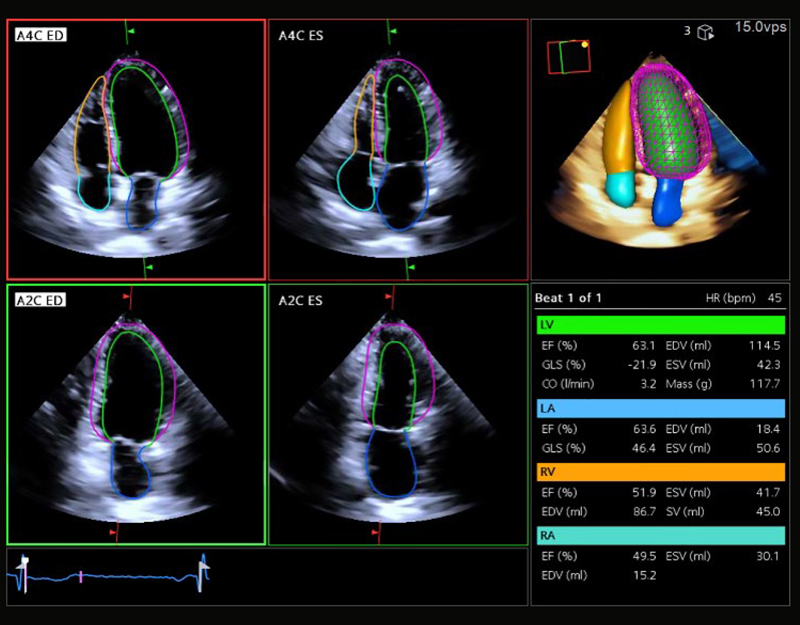

• 4D Heart: tracciamento automatico in 3D/4D di tutte e quattro le camere con la nuova sonda cardiologica a matrice e ricostruzione 3D/4D automatica

Con un clic, anche senza ECG, permette la rilvazione automatica del bordo endocardico delle 4 camere cardiache con generazione automatica del rendering 3D/4D.

Misura del GLS Totale di tutte le 4 camere, e GLS segmentario delle sezioni di sinistra con creazione del Bull’s-Eye.